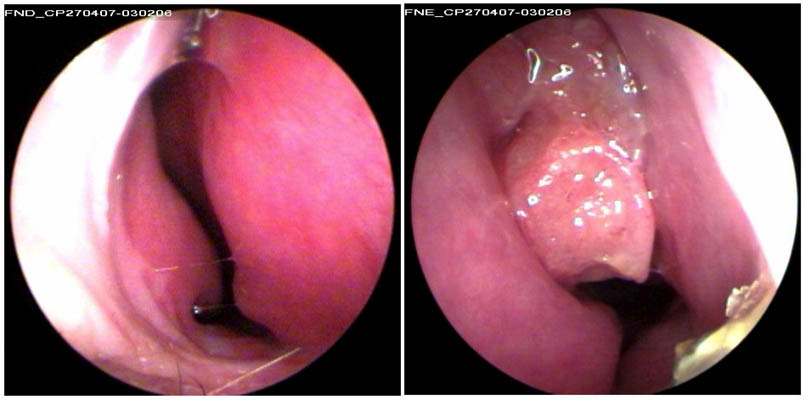

JFC Poliposis nasal bilateral.